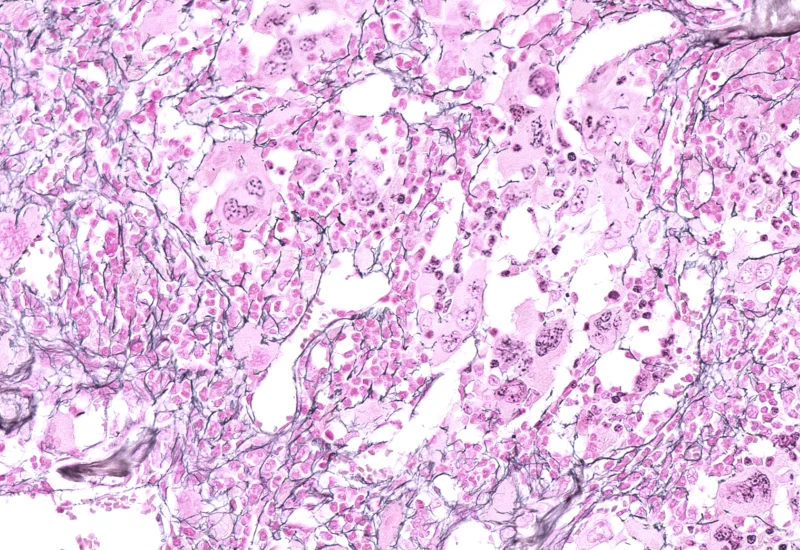

IHC Extracellular Filaments

Detect nuclei and extracellular filaments in IHC-stained sections, and quantify nuclei number, total filament area, and filament length.

The IHC Extracellular Filament App detects nuclei as well as extracellular filaments stained with specific markers. It outputs the number of nuclei, the total gilaments area and the lenght of the filaments.

Original Image